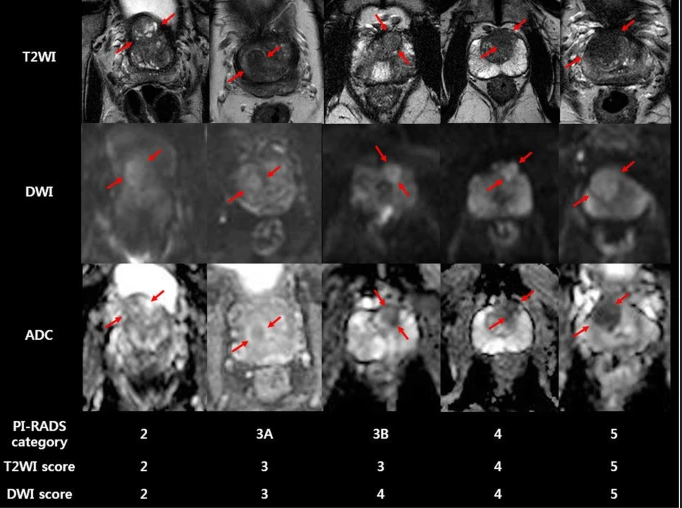

7

PI-RADS zona transicional? (5)

A

1:Zona de transição com aspecto normal (raro)

ou nódulo arredondado, completamente encapsulado (nódulo típico de HPB)

2:Nódulo majoritariamente encapsulado

ou nódulo homogêneo circunscrito sem cápsula (nódulo atípico)

ou área homogênea levemente hipointensa entre nódulos

3:Sinal heterogêneo com margens mal definidas

(inclui lesões que não se encaixam em 2, 4 ou 5)

4:Lesão lentiforme ou não circunscrita, homogênea,

moderadamente hipointensa, < 1,5 cm

5:Igual ao 4, porém:

≥ 1,5 cm

ou extensão extraprostatica / comportamento invasivo.

(Zona de Transição (ZT) – Sequência dominante: T2)

Exemplos de câncer de próstata na zona de transição interpretados segundo a PI-RADS v2.1.